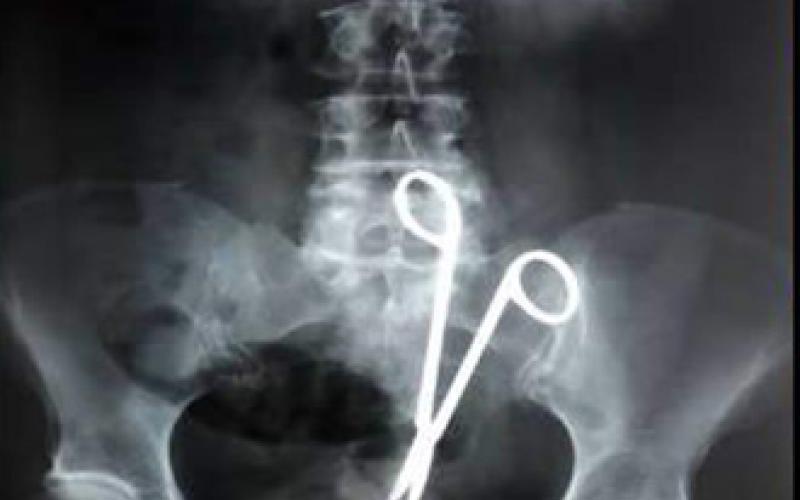

وتقول ميرفت ان مشوارها بدا عند هذه اللحظة وحسب التقرير فان العملية قد اجريت متأخرة حيث كان الطبيب الاختصاصي المناوب قد عاد الى منزله وبسبب ما حدث من خطأ فقد اجريت لي 5 عمليات في شهر وكانت اول عملية ولادة الجنين قيصرية والعملية الثانية استئصال الرحم بالخطأ وتبين ان النزيف ليس بسبب الرحم وانما جراء اصابة احد الاوردة الفرعية بنزف اما العمليات الثلاث الاخرى فقالت عنها كنت قد عدت للمستشفى بعد ان تبين ان الطاقم الذي اشرف على وضعي نسي قطعة شاش في بطني فاجريت لي عملية وغادرت المستشفى الا ان الما في البطن ظل ملازما لي وعدت الى المستشفى وتم تصويري شعاعيا ولم ابلغ وقتها باي شيء وعدت الى منزل عائلتي في وادي موسى الا ان زوجي تلقى اتصالا من المستشفى يطلب عودتنا حيث كان قد اكتشف بالصورة قسطرة على الكلى جراء خطأ الطبيب خلال استئصال الرحم بتقطيب الحالب بغرزة وتم اجراء قسطرة على الكلى حيث اجريت عملية ازالة للقسطرة .